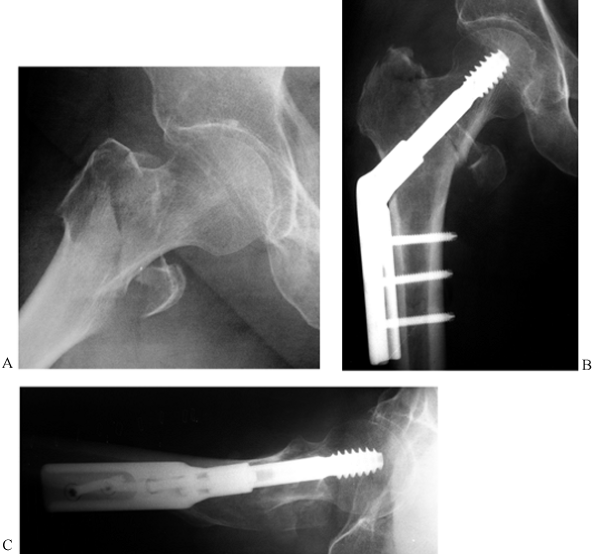

![]() |

Figure 19.6. Cannulated screw fixation of a displaced subcapital hip fracture: A: AP radiograph showing a fully displaced Garden stage IV subcapital fracture. B: Lateral radiograph of the displaced fracture. C: AP radiograph after closed reduction and cannulated screw fixation. D: Lateral radiograph after fixation.

|